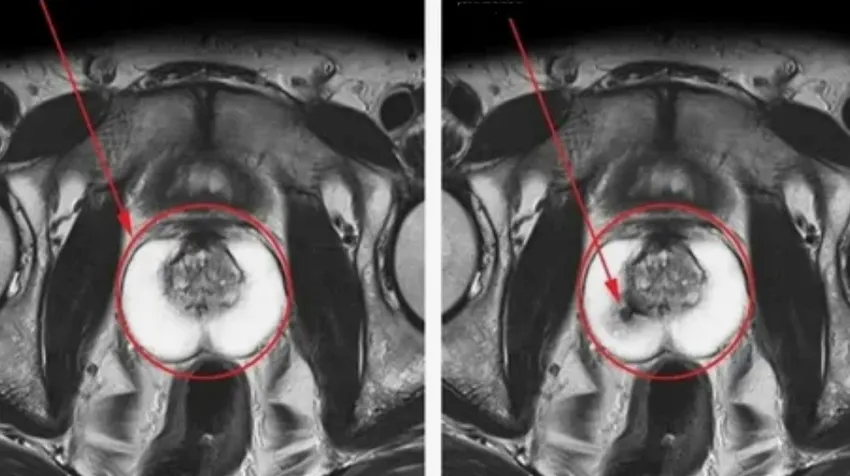

Так виглядає рак простати